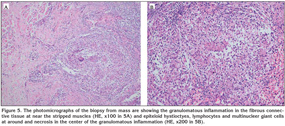

A 18-year-old Georgian male patient was admitted to the hospital with swelling above the eye, double vision, swelling and wound on the 3rd digit of the right hand. His physical examination revealed a palpable and readness mass lesion above the left eyelid (Figure 1). There was an edema, swelling and ulcerated wound on the soft tissue of the mid phalanx of the left third digit (Figure 2A). There were no relevant findings in the patient's history. A hand radiography showed the cystic appearance with expansion named "spino ventosa" in the bone tissue of the left third digit (Figure 2B). There were no abnormalities in his laboratory values. Sedimentation was 41 mm/hour. The patient underwent PPD test, which was positive. He was HIV-negative. Cranial MR was performed and a extraconal mass lesion was detected in diameter of 22 x 28 x 30 mm on the left orbita. The lesion was extending from the frontal to maxillary region (Figure 3). The lesion was localized in bone structures and subcutaneous tissue and was compressing to the left eye globe and extraocular muscles. CT of the thorax was taken, which showed fibrotic chronic infiltration and nodular lesions in the lung parenchyma and paravertebral hypodense lesions with loculi with a diameter of approximately 4 cm extending from the superior thoracic level downwards (Figure 4). Bronchoscopy revealed the edeumatous narrowing on the right upper bronchus. Acid-fast bacilli was negative by microscopic examination of bronchial lavage fluid. Excisional biopsy was performed from the mass on the patient's left eyelid and the histopathologic analysis showed "caseified granulomatous inflammation"(Figure 5). Based on the clinical, radiologic and pathologic findings, the patient was diagnosed with tuberculosis. The improvement was observed with antituberculosis treatment at lesions and symptoms of patient. The approval of patient and institution were taken to use their records for our study.

Differently from pulmonary tuberculosis, diagnosis in patients with extrapulmonary tuberculosis is usually made with the histopathologic evaluation. The diagnosis is established after determining granulomatous inflammation including caseification necrosis in the biopsy extracted from the affected region. Improvement obtained after starting the anti-tuberculous treatment also supports the accuracy of diagnosis. A rapid improvement was observed in our patients with antituberculosis treatment at lesions and symptoms of patient.